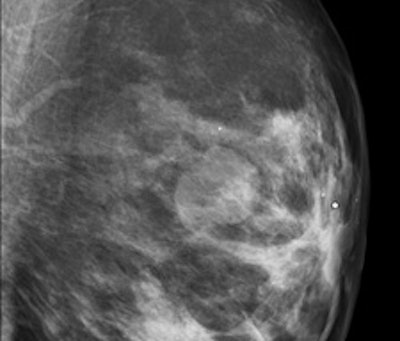

After detection of a possible lesion using a front-line method such as standard two-view mammography, additional techniques should be used if there is reasonable suspicion of cancer. Superimposed breast tissue can mimic a malignant lesion. If the lesion exists, other techniques can help the radiologist to decide about the degree of concern and to classify the lesion correctly. These were discussed during Friday's session. In addition, speakers covered the influence of clinical data on classification.